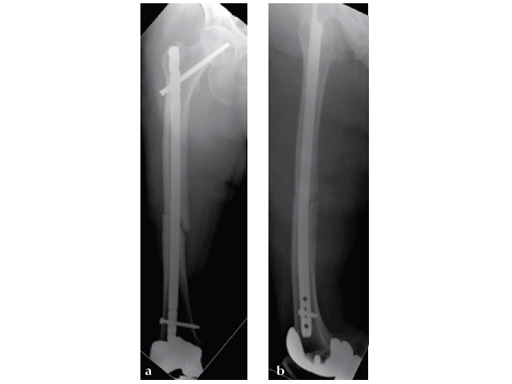

Notice the fracture decrease the emphasis on the anterolateral bow of the femur (See Fig 5a-b).

Insertion of A2FN as patient may be suffering from a stress fracture related to long term (2.5 years) bisphosphonate use. My rationale against a plate is because bisphosphonate related fractures will heal extremely slowly. In our experience even despite bone grafting union may need up to 2 years. In that time, a plate will fail in less than a year even if the patient is only allowed very minimal weight bearing.

Note despite the increased in curvature compared to other nails in the market, there is still noticeable malreduction at the fracture site (see Fig 6a-b).